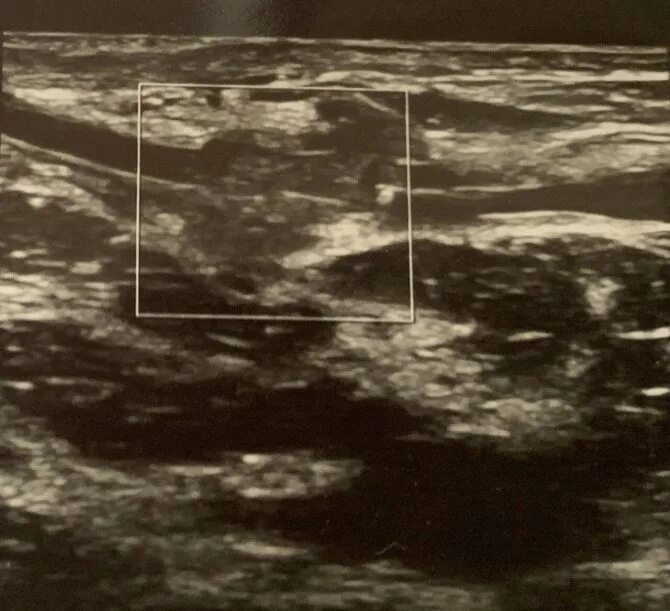

Выделение из молочных желез форум